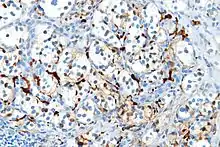

Varios miembros de la familia de proteínas S100 son útiles como marcadores para determinados tumores. Pueden ser encontradas en melanomas, en el 100% de schwannomas, 100% de neurofibromas (de forma más débil que en los schwannomas), 50% de los tumores malignos de la vaina de nervios periféricos (de forma débil y/o focal), histiocytoma y célula clara sarcomas.[8] Además, las proteínas S100 son marcadores de enfermedades inflamatorias. También puede mediar en la inflamación y actuar como antimicrobianos.[9]